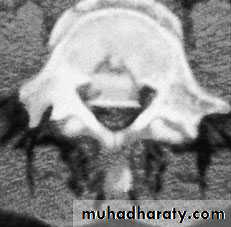

Axial compression or burst injury

Severe axial compression may ‘explode’ the vertebral body, causing failure of both the anterior and the middle columns. The posterior column is usually, but notalways, undamagedAnteroposterior x-rays may show

spreading of the vertebral body with an increase of the interpedicular distance

Posterior displacement of bone into the

spinal canal (retropulsion) is difficult to see on the plain lateral radiograph; a CT is essential.